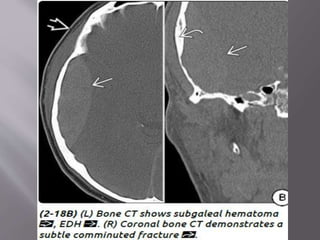

4) Bone CT- Look for

a) basisphenoid fractures with involvement of the

carotid canal,

b) temporal bone fractures (with or without

ossicular dislocation)

c) mandibular dislocation ("empty" condylar fossa)

d) calvarial fractures.

1) Epidural hematoma- two types : arterial EDH and

venous EDH. EDH r uncommon but r potentially

lethal. 90% EDH r arterial , 10% r venous. Venous

EDH r sec. to a fracture that crosses dural venous

sinus (transverse/sig , SSS)

lacerates an adjacent artery(mc’ly-mma)

mostly unilateral and supratentorial. Squamous

portion of temporal bone is the most common site.

Biconvex in shape, doesnt crosses suture line, but

if fracture crosses suture line……